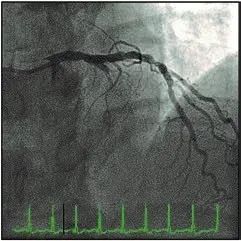

11.全动脉血管重建和非全动脉血管重建的远期预后对比(JAMA Cardiol 2020 Feb 19[Epub ahead of print].)

移植物的选择可能影响冠状动脉旁路移植术(CABG)的结果。

这项基于人群的回顾性队列研究,纳入49,404例原发性单支病变的CABG患者,比较全动脉血管重建与非全动脉血管重建(CABG至少有一条动脉和一条隐静脉移植)的长期临床预后。

纳入者进行倾向评分匹配,平均追踪观察4.6年,最长观察9年。虽然两组患者的搭桥次数相似,但全动脉血管重建组的动脉移植物更多(平均值:2.4 VS 1.2,P < 0.01)。

两组住院死亡数相近(全动脉血管重建组15例,非全动脉血管重建组12例,P =0.32)。超过8年,全动脉血管重建组比非全动脉血管重建组重大不良脑血管和心脏事件的发生率较低(危险比0.78[95%CI,0.68-0.89])。

全动脉血管重建组总死亡人数(危险比0.80[95%CI,0.66-0.97])和心肌梗死(危险比0.69[95%CI,0.51-0.92])均较少。两组发生脑卒中与需要再次血管重建的比例差异无统计学意义。

(文章选择: Martin J. London. 图片: J. P. Rathmell.)

关键信息:CABG患者中,全动脉血管重建可减少脑血管和心脏不良事件、死亡和心肌梗死的发生。